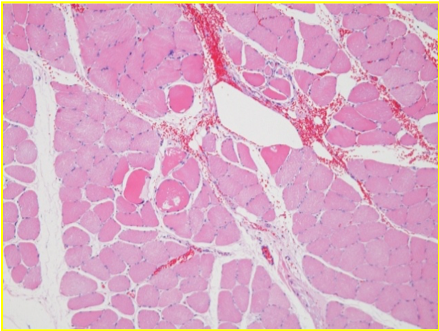

disorganization seen 25 min post endopeel

reorganization 60 min after endopeel

after 0.05 ml endopeel injection